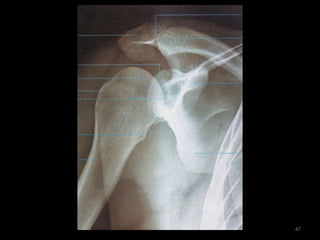

Incidência Oblíqua Apical – Rockwood (3)45

46

47